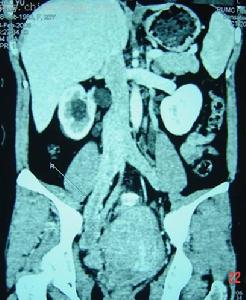

病變圖樣 1.陰道脫落細胞塗片檢查是陰道上皮內腫瘤初步篩選的有效方法。凡是陰道 細胞學塗片異常,應排除該異常細胞是否來自宮頸或外陰。

2.當陰道細胞學出現 異常時需行陰道鏡檢查。陰道鏡下常可發現陰道上皮出現白色鑲嵌狀點滴狀和微粒狀的表 現。

3.凡陰道黏膜上有明顯的病灶,可直接行活檢送病理檢查如陰道黏膜無明顯 異常可在陰道鏡或碘液塗抹陽性處行活檢送病理檢查。